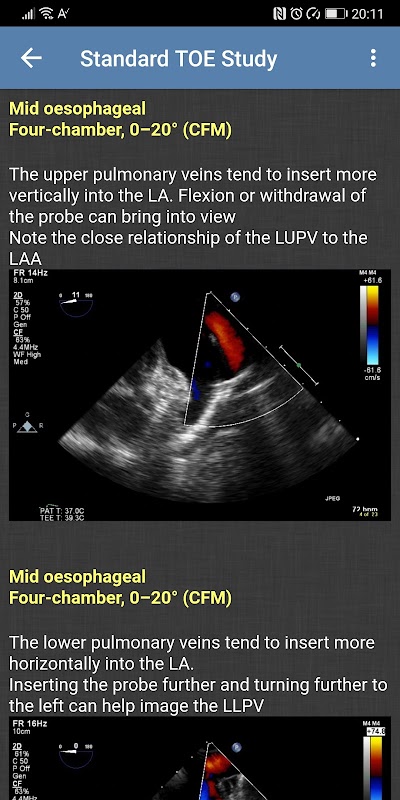

- Standart TOE Çalışması